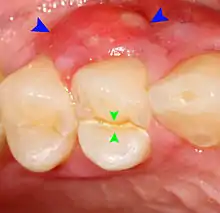

Lateral periodontal abscess (blue arrows) due to a fracture (green arrows)

A periodontal abscess (lateral abscess) is a collection of pus that forms in the gingival crevices, usually as a result of chronic periodontitis where the pockets are pathologically deepened greater than 3mm. A healthy gingival pocket will contain bacteria and some calculus kept in check by the immune system. As the pocket deepens, the balance is disrupted, and an acute inflammatory response results, forming pus. The debris and swelling then disrupt the normal flow of fluids into and out of the pocket, rapidly accelerating the inflammatory cycle. Larger pockets also have a greater likelihood of collecting food debris, creating additional sources of infection.[21]:443

Periodontal abscesses are less common than apical abscesses, but are still frequent. The key difference between the two is that the pulp of the tooth tends to be alive, and will respond normally to pulp tests. However, an untreated periodontal abscess may still cause the pulp to die if it reaches the tooth apex in a periodontic-endodontic lesion. A periodontal abscess can occur as the result of tooth fracture, food packing into a periodontal pocket (with poorly shaped fillings), calculus build-up, and lowered immune responses (such as in diabetes). Periodontal abscess can also occur after periodontal scaling, which causes the gums to tighten around the teeth and trap debris in the pocket.[21]:444–445 Toothache caused by a periodontal abscess is generally deep and throbbing. The oral mucosa covering an early periodontal abscess appears erythematous (red), swollen, shiny, and painful to touch.[22]